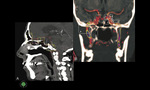

– Naszą specyfiką jest oczodół – dodaje prof. Mariak. – To obszar, który jest wypełniony tłuszczem, w którym leżą drobne, ale bardzo ważne nerwy i naczynia. Dlatego wszyscy do niedawna omijali go z operacjami. My jako jedni z pierwszych w świecie zaczęliśmy tam dostawać się endoskopem. Przeznosowy dostęp do oczodołu może się odbywać przez jego ścianę przyśrodkową po usunięciu komórek sitowych lub ścianę dolną, po otwarciu zatoki szczękowej od strony nosa (ryc. 3). Operując w oczodole za pomocą endoskopu, nie należy przekraczać linii nerwu wzrokowego, a więc z dostępu przeznosowego w zasięgu chirurga będą tylko zmiany zlokalizowane w przyśrodkowej części oczodołu. Natomiast do zmian położonych w dolnej części oczodołu konieczny jest dostęp „podwójny”, co oznacza wykonanie dodatkowego dojścia przez przednią ścianę zatoki szczękowej lub przez przegrodę nosa. Ten dodatkowy dostęp umożliwia równoległą pracę drugiemu chirurgowi. Pozostaje jednak część boczna i górna oczodołu, do której dotychczas nikt skutecznie nie wchodził za pomocą endoskopu. Szczególnym osiągnięciem zespołu białostockiego jest opracowanie, praktyczne zastosowanie i opublikowanie w światowych czasopismach własnych koncepcji dojść endoskopowych do tych dotychczas „zakazanych” dla endoskopii przedziałów oczodołu. Są to różne odmiany dojść przezspojówkowych oraz w pełni endoskopowe, a zatem dużo mniej inwazyjne wykonanie znanej w okulistyce operacji Krönleina.